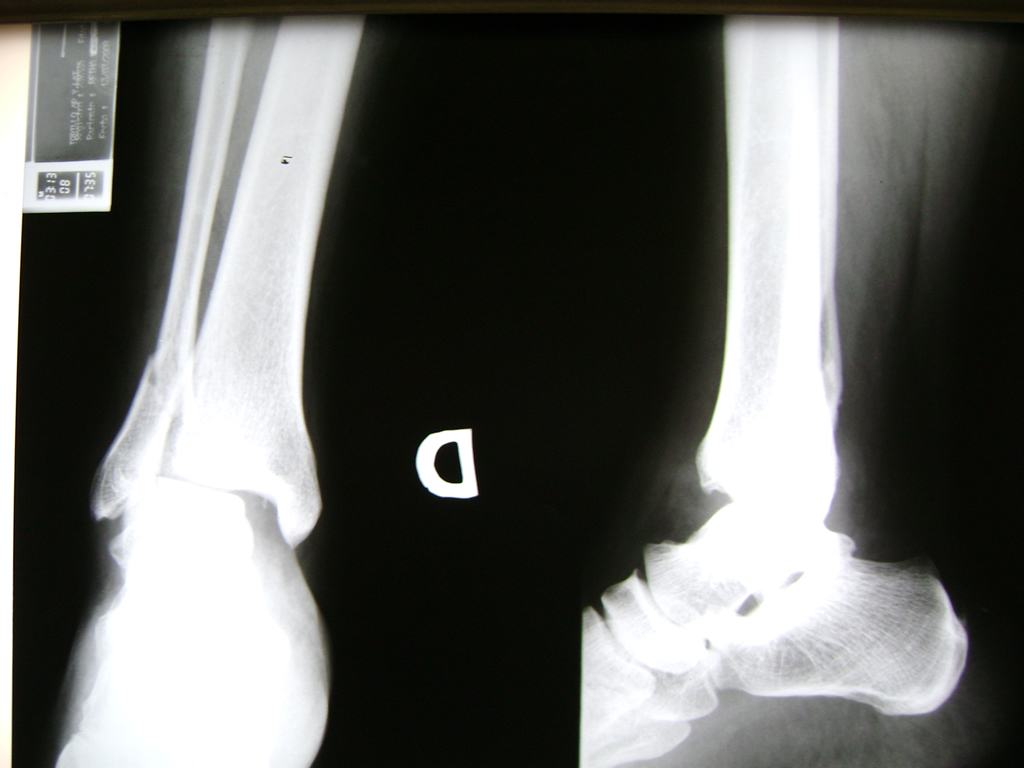

Una fractura de tobillo es la rotura de uno o más de los huesos del tobillo. Estas fracturas pueden ser:

- Parciales (el hueso está sólo parcialmente fisurado, no del todo).

- Completas (el hueso está perforado y está en 2 partes).

- Producirse en uno o ambos lados del tobillo.